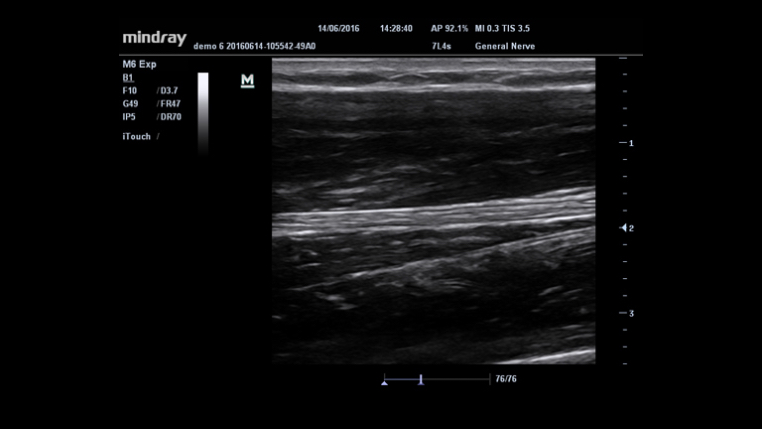

iNeedle?

Doskona?e narz?dzie do wykonania biopsji: pozwala na dopasowanie k?ta linii skanowania w celu uzyskania lepszej widoczno?ci ig?y, nerwów i drobnych naczyń krwiono?nych.